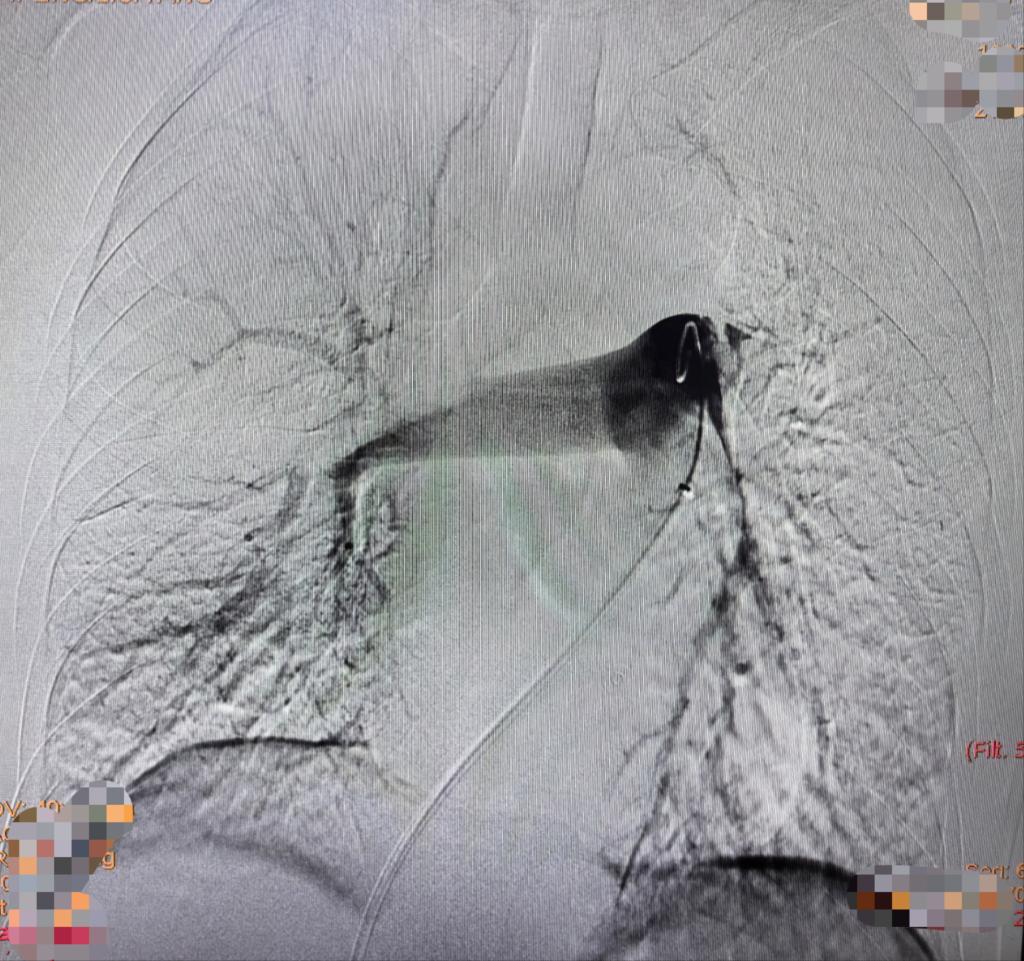

患者入院时,门诊CTPA提示:双肺动脉主干肺栓塞,伴有右心房栓子(性质不确定)、下肢深静脉血栓,经急诊抢救室初步评估为肺栓塞(高危)立即收住EICU。急诊科裴红红主任立即组织EICU李萍教授、急诊科介入团队彭卓副主任、古长维副教授评估患者后,决定给予患者行经导管肺动脉机械取栓术,这样不仅能够抽吸肺动脉栓子,同时能够明确右心房及肺动脉栓子性质。在影像科积极协助下,术中下腔静脉造影见下腔静脉血栓附着,通过精准定位行下腔静脉滤器置入。然后,肺动脉造影,见双肺显影不佳,左肺为著,测肺动脉压50mmHg,行肺动脉血栓抽吸术,术中明确栓子性质为血栓,行肺动脉造影,双肺显影明显改善,复测肺动脉压39mmHg,遂于肺动脉主干留置导管后持续24小时溶栓治疗。后续持续抗凝,患者症状明显改善,2日后转入普通病房,并自由活动,复查心脏B超:右心房未见血栓,现患者已康复出院。

抽栓前造影